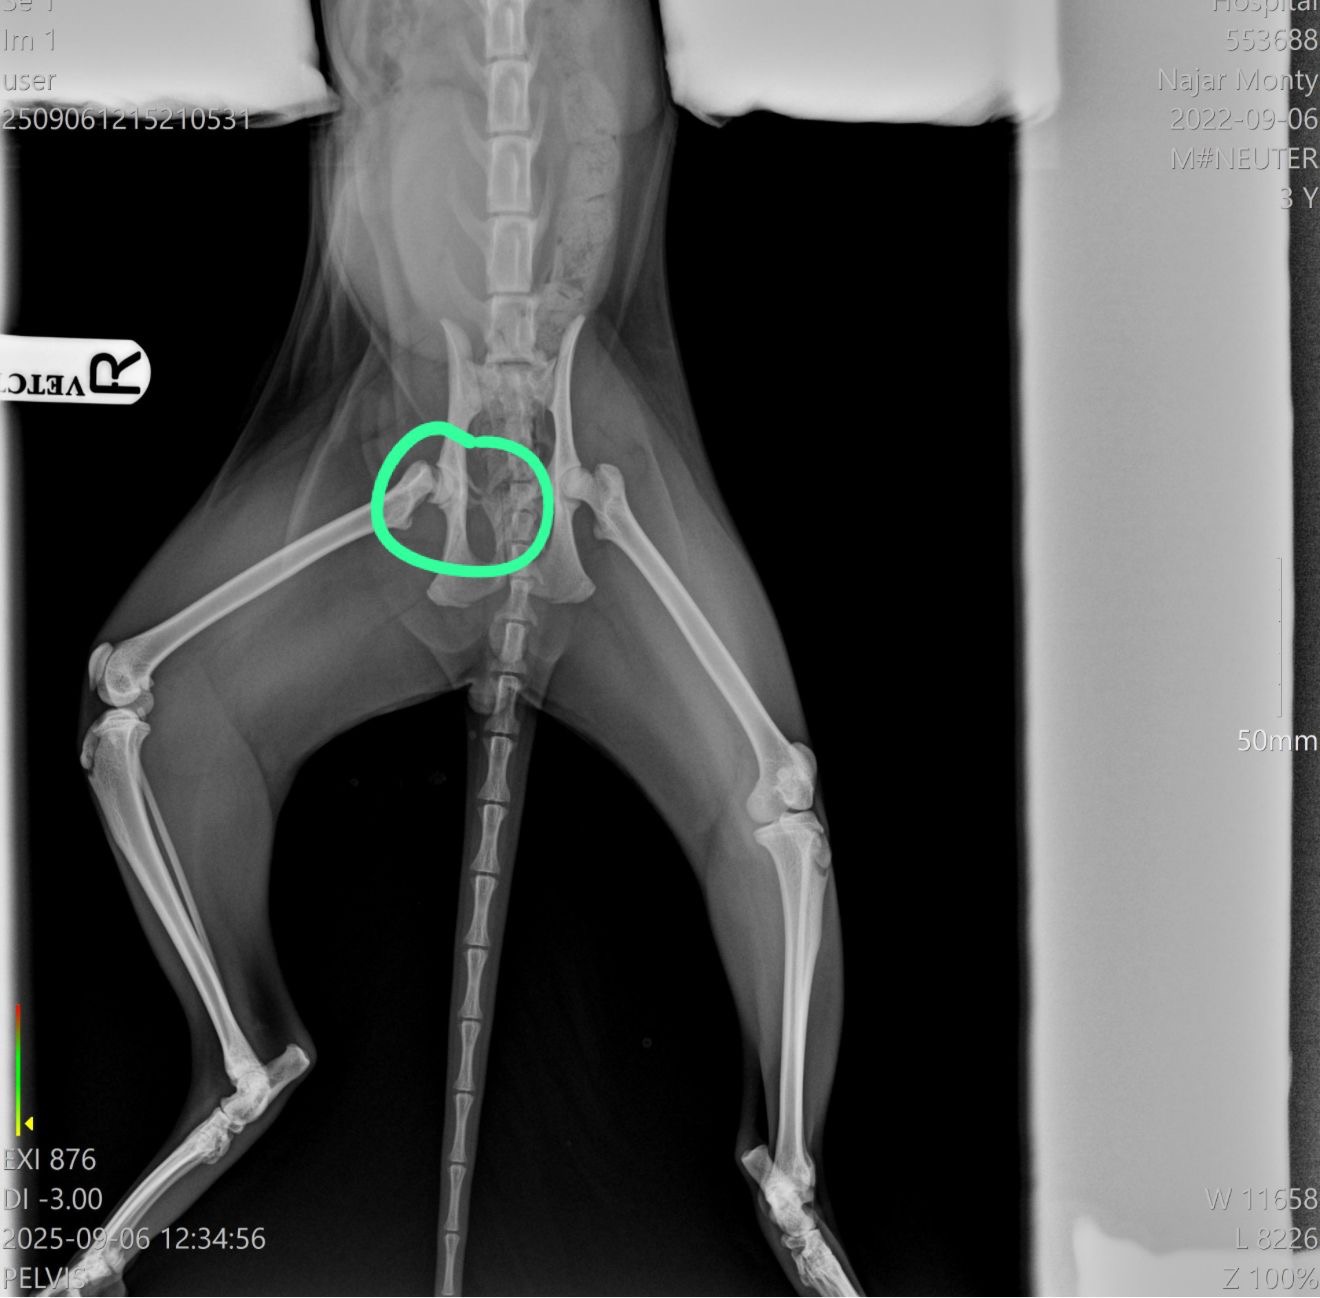

Two months ago, our darling cat Monty had an accident and fractured his pelvis. After eight weeks of crate rest, we’ve learned that he still needs surgery to recover properly and live without pain.